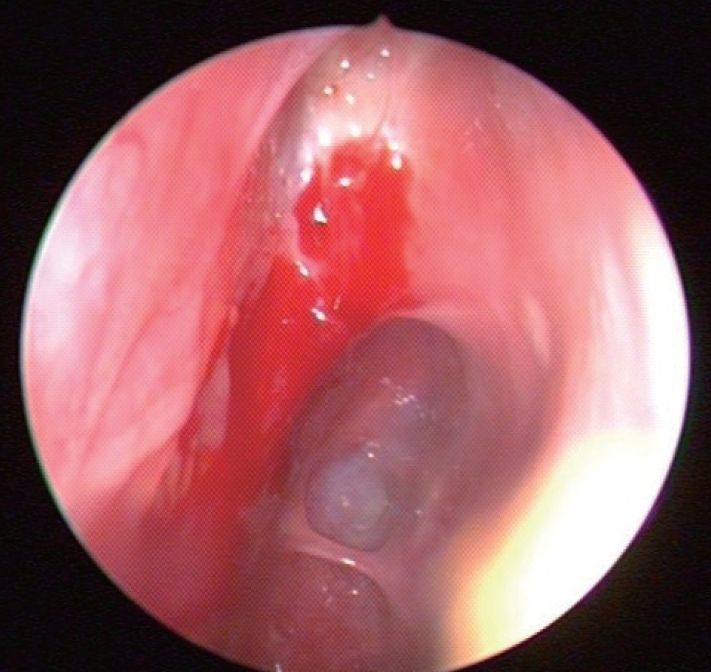

CaseA 59-year-old male presented to the emergency department with profound lethargy, progressive headache, personality changes and mood swings. The symptoms had developed since the last 1 week. The patient had a history of diabetes and depressive disorder, which was diagnosed recently based on the above mentioned symptoms; and he had undergone ESS 6 weeks ago. He had visited our outpatient clinic with a 2-month history of nasal obstruction and epistaxis. He had already been diagnosed as having chronic rhinosinusitis and nasal polyps, but there was no response to medical treatment. In the contrast computed tomography (CT) scan of his paranasal sinuses, there was a soft tissue mass that had completely filled the right maxillary sinus and was extending into the nasal cavity with widening of the maxillary ostium, the ethmoidal infundibulum, and lifting of the ethmomaxillary plate. This mass was diagnosed as inverted papilloma (Fig. 1). He underwent right endoscopic medial maxillectomy under general anesthesia and the diagnosis of inverted papilloma was confirmed by frozen biopsy. Intraoperatively, it was noted that the mass was penetrating into the anterior skull base and there was a 1.5-cm dural defect resulting in CSF leakage following the surgery. The defect was repaired using an underlay technique with the inferior turbinate mucosal flap, and the septal cartilage was sealed with a fibrin sealant Tissucol Duo Quick® (Baxter AG, Vienna, Austria). The lumbar drain was maintained for 3 days postoperatively. He was discharged from the hospital on the seventh day after surgery. During the follow-up period, 3 days before the visiting the emergency room, he complained of non-locaized mild headache and mild lethargy. Also, no obvious CSF leakage was detected on nasal endoscopy (Fig. 2).

In the emergency room, he was found to be confused, but was following commands, and was oriented to person and place. On neurologic examination, his Glasgow Coma Scale score was 15. He showed normal pupillary reflexes, normal motor and sensory functions in all 4 extremities, normal deep tendon reflexes. A non-contrast CT scan of his brain was performed, and it showed significant air collection in the right frontal area and also a midline shift (Fig. 3). He was diagnosed with a tension pneumocephalus and referred to the neurosurgery department. Then, he underwent a bifrontal craniotomy for tension pneumocephalus. During the operation, we found adhesions between the nasal mucosa and dura mater, but there was no defect between nasal mucosa and dura and no CSF leakage. After detaching these adhesions, duroplasty and cranioplasty were performed. Postoperative conservative treatment was applied, including bed rest, meningitis prophylaxis, maintenance of extraventricular drainage. In the follow-up CT taken at 2 weeks after the surgery, resolution of tension pneumocephalus was observed (Fig. 4). His condition was stable and he showed a normal mental status, not confused. He was discharged 14 days after the surgery. In an endoscopic examination performed in the 2nd month, there was no skull base defect or CSF leakage (Fig. 5). The patient did not have any complaints or symptoms for 6 months after the surgery.

NotesAuthor Contribution Conceptualization: Jin Kook Kim. Data curation: Hansol Kim, Taesik Jung. Formal analysis: Hansol Kim, Taesik Jung, Jin Kook Kim. Methodology: Jin Kook Kim. Project administration: Joon Yong Park, Jin Kook Kim. Supervision: Jin Kook Kim. Visualization: Hansol Kim, Taesik Jung. Writing—original draft: Joon Yong Park. Writing—review & editing: Jin Kook Kim. Fig. 1.In the CT scan of paranasal sinuses, the right maxillary sinus was filled with a heterogeneous soft tissue mass. The mass was extending into the nasal cavity with widening of the maxillary ostium. Fig. 2.Endoscopic finding of the dural repair site. There was no cerebrospinal fluid leakage at postoperative 6 weeks. REFERENCES1. DelGaudio JM, Ingley AP. Treatment of pneumocephalus after endoscopic sinus and microscopic skull base surgery. Am J Otolaryngol 2010;31(4):226-30.